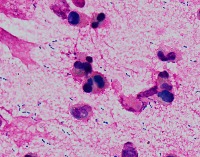

Medical Research: This model can be utilized in the field of medical microbiology and research to classify bacterial strains based on their visual characteristics in lab experiments and for the study of bacterial growth processes.

Healthcare Diagnostics: In healthcare, the "assembly" model could be used to assist in bacterial diagnosis in clinical lab settings, identifying the presence of specific forms of bacteria like Staphylococcus, Streptococcus, B-catarrhalis, Str_pne, and Enterococcus in samples.

Pharmaceutical Industry: The model could be applied in the development stages of antibiotics or bacterial treatments, helping to identify and study the response of specific bacterial strains to new drugs.

Educational Tools: Educators and students could employ the model as a learning tool for illustrating bacterial species classes, supplementing traditional teaching methods in biology or medicine related courses.